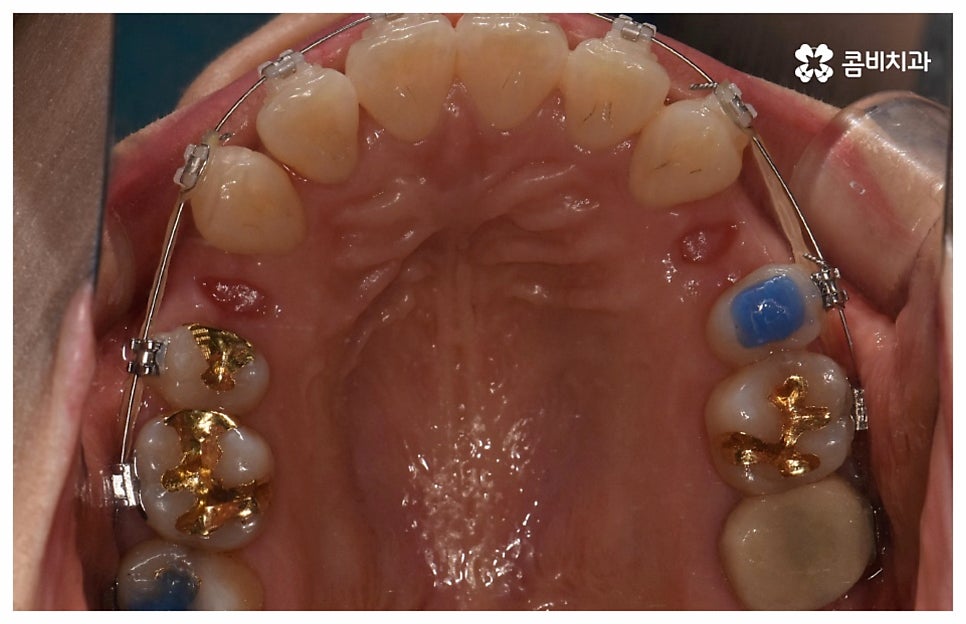

검진 후 부분 교정이 가능하지 않은 케이스라고 해도 요즘은 심미적인 교정 장치가 많이 나와 있으며 장치 자체로 인해 결과에 미치는 영향이 크지 않기 때문에 자신의 상황에 맞는 장치를 직접 선택할 수 있으니 의료진과 충분히 상담을 해 보시면 도움 받아 보실 수 있을 거예요. 특히 치아 색상의 브라켓을 이용한 세라믹 장치들이 심미성이 뛰어난데, 그 중에서도 자가결찰방식을 이용한 클리피씨 교정 장치를 이용하면 눈에 크게 띄지 않을 뿐 아니라 보다 적은 힘으로 부드럽고 지속적인 치아 이동을 가능하게 하기 때문에 통증도 줄이고 전체 교정 기간 역시 단축시킬 수 있다는 장점이 있으니 이에 대해서도 자세하게 알아보시길 바라고 있습니다.

위 사진은 환자분의 동의를 받아 이해를 돕기 위한

사진이며, 실제 치료 결과는 다를 수 있습니다.